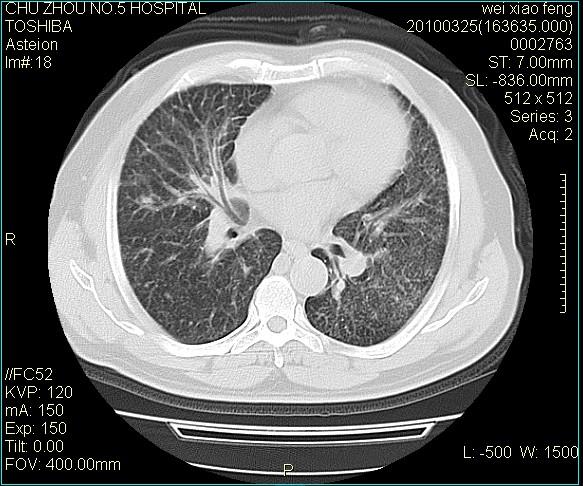

男,60岁,反复咳、痰、喘3月,加重3天。

双肺间质性改变。

考虑双肺血型潘散肺结核/

间质性肺炎伴间质纤维化!不排除伴有职业病!

急性血型潘散肺结核。

双肺间质纤维化,双肺血型潘散肺结核。

考虑间质性肺炎伴间质纤维化。

右肺中叶结节影为原发灶,考虑右肺中叶周围型肺癌并淋巴道转移